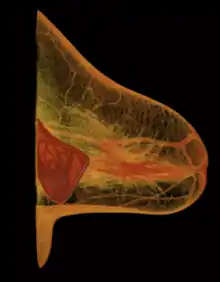

- Prepectoral or subcutaneous: in a breast reconstruction following a skin-sparing or skin- and nipple-sparing mastectomy, the implant is placed above the pectoralis major muscle without dissecting it so that the implant fills directly the volume of the mammary gland that has been removed. To avoid the issue of capsular contracture, the implant is often covered frontally or completely with a mesh in biomaterial, either biological or synthetic.